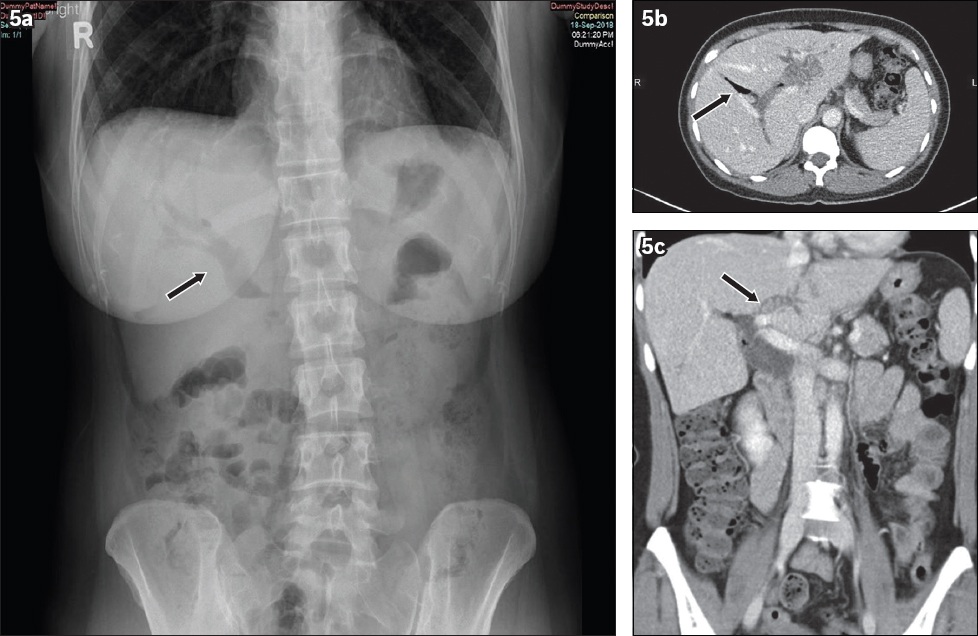

Fig. 5

Pneumobilia. A 42-year-old woman presented with right hypochondrium pain. (a) Erect abdominal radiograph shows branching linear lucencies projected over the intrahepatic and common bile ducts (black arrow). (b) Contrast-enhanced axial CT image of the abdomen demonstrates severe intra- and extrahepatic biliary dilation with centrally located gas (black arrow) in contrast to the typical, peripheral location of portal venous gas. (c) Contrast-enhanced coronal CT image shows several small iso-attenuating calculi within the left main intrahepatic biliary duct (black arrow). No other obstructing lesion within the common bile duct is noted.